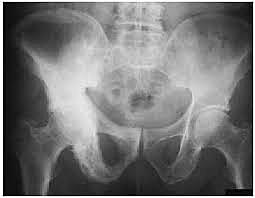

• RAYOS X DEL SISTEMA ÓSEO

Alban Köhler, que en 1910 publicó un importante

libro titulado "Enciclopedia de los límites normales en las imágenes de Röntgen". Köhler, fue un editor prolífico de artículos sobre radiología ósea. Pronto se dio cuenta de que, mediante el uso de rayos X, era posible examinar problemas reumáticos congénitos, además de afecciones metabólicas anormales y trastornos de osificación del esqueleto (European Society of Radiology, 2012)